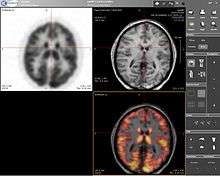

Computer screenshot showing a PET image (upper left), MRI image (upper right) and the combined PET-MRI image where PET data is overlaid over the MRI data (lower right)

Positron emission tomography–magnetic resonance imaging (PET-MRI) is a hybrid imaging technology that incorporates magnetic resonance imaging (MRI) soft tissue morphological imaging and positron emission tomography (PET) functional imaging.[1]